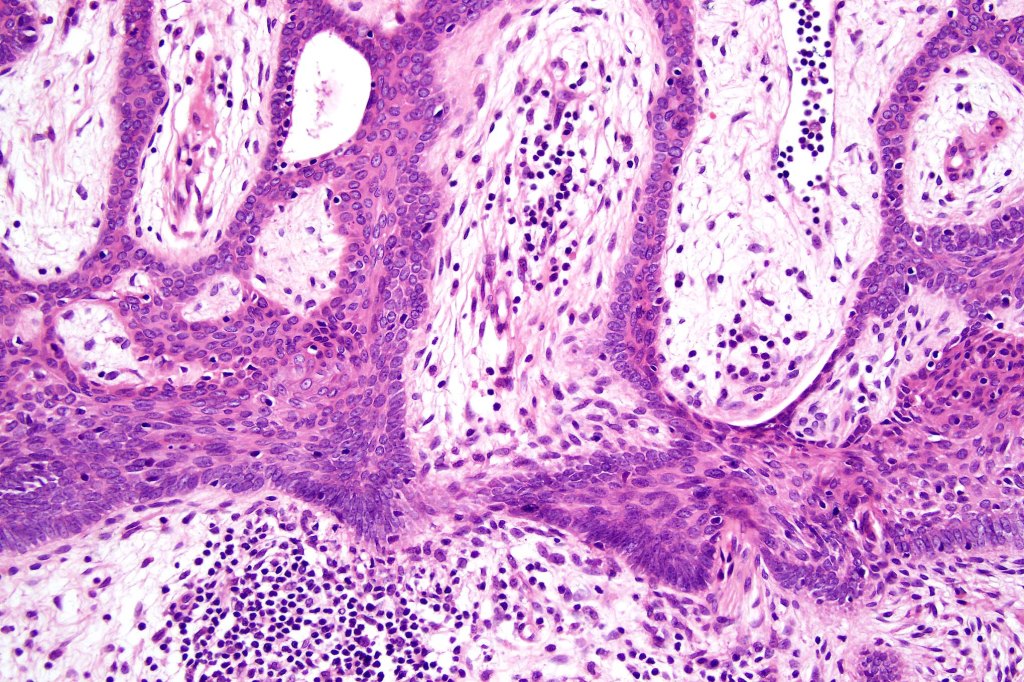

Histological features

•Characteristic fenestrated epithelial plate-like silhouette suspended below the epidermis

•Pale-staining epithelial cells with peripheral palisading

•Eosinophilic basement membrane

•No pleomorphism or mitotic activity